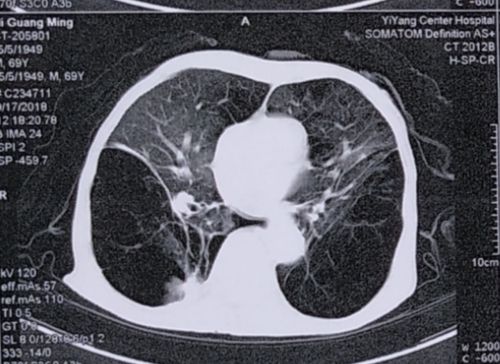

1月后(9-17)复查胸部ct,右下肺大泡较前明显复张.